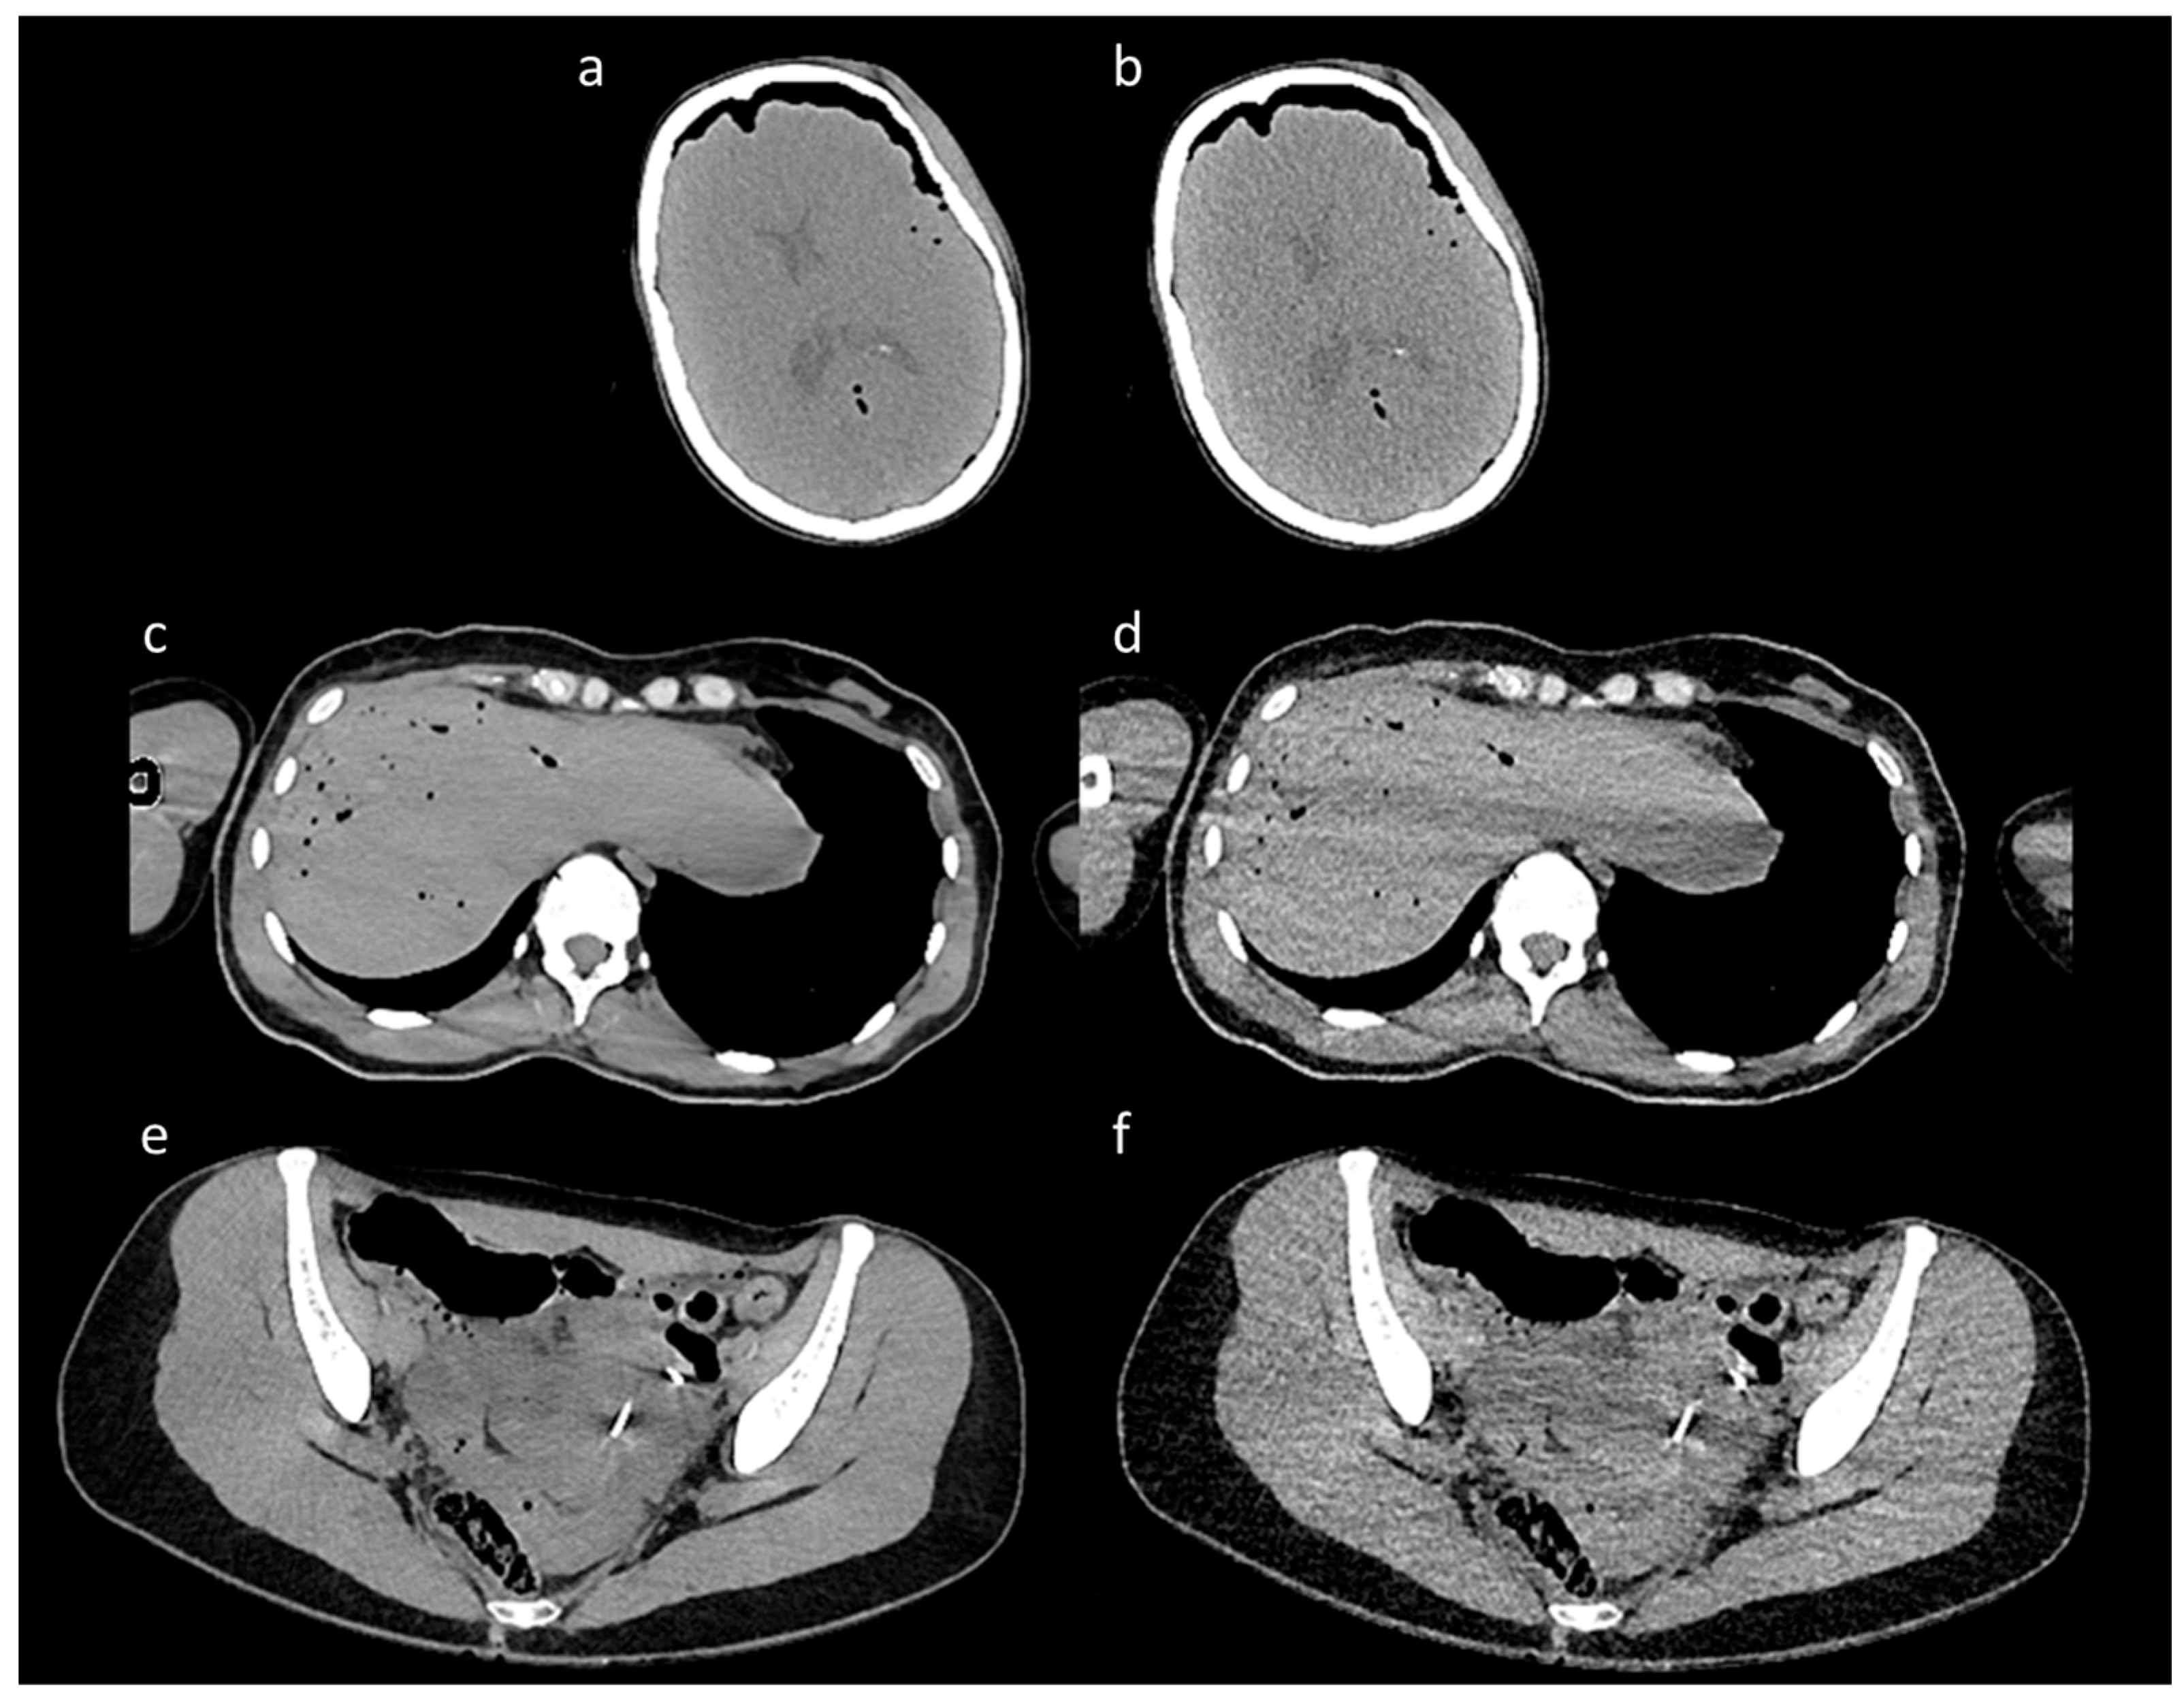

The scans encompassed a range of body dimensions representative of diverse patient anatomies, with heights ranging from 142 cm to 204 cm and varying body compositions, including a broad spectrum of body mass indices (BMI 18–32). The CT images were reconstructed using the Iterative Reconstruction technique, generating pairs of high-quality (HQ) and low-quality (LQ) images for each scan (Figure 1). Specifically, low-dose (LQ) scans exhibited significant noise levels, while high-dose (high-quality) scans served as a reference standard with low noise.

Figure 1.

Representative paired CT images from the training set. The figure shows a representative selection of paired CT images from the training dataset. The figure is organized into three pairs, each featuring a high-dose image and its corresponding low-dose counterpart. The high-quality images, shown in panels (a,c,e), served as clean reference targets for the model, while the LD images in panels (b,d,f) were used as noisy inputs. The paired images come from three distinct anatomical regions: (a,b) show a scan of the skull, (c,d) show a scan of the abdomen at the level of the liver, and (e,f) illustrate a scan of the pelvis.